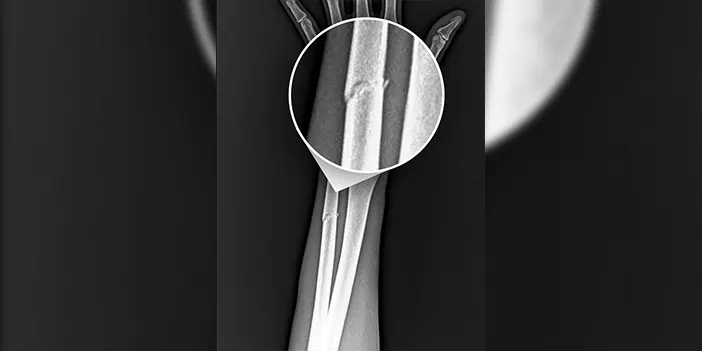

Trabzonspor, Ziraat Türkiye Kupası Çeyrek Finalinde Başakşehir maçında kolu kırılan Paul Onuachu ile ilgili açıklamalarda bulundu.

“Futbol A Takımımızın RAMS Başakşehir ile oynadığı karşılaşma esnasında sakatlanarak oyundan çıkan futbolcumuz Paul Onuachu’nun yapılan muayenesinde sol kasık bölgesinde kas (adduktor kas grubu) yaralanması ve sol önkolda darbeye bağlı ayrışmamış kemik (ulna) kırığı tespit edilmiştir. Oyuncumuzun tedavisine sağlık ekibimizce başlanılmıştır”